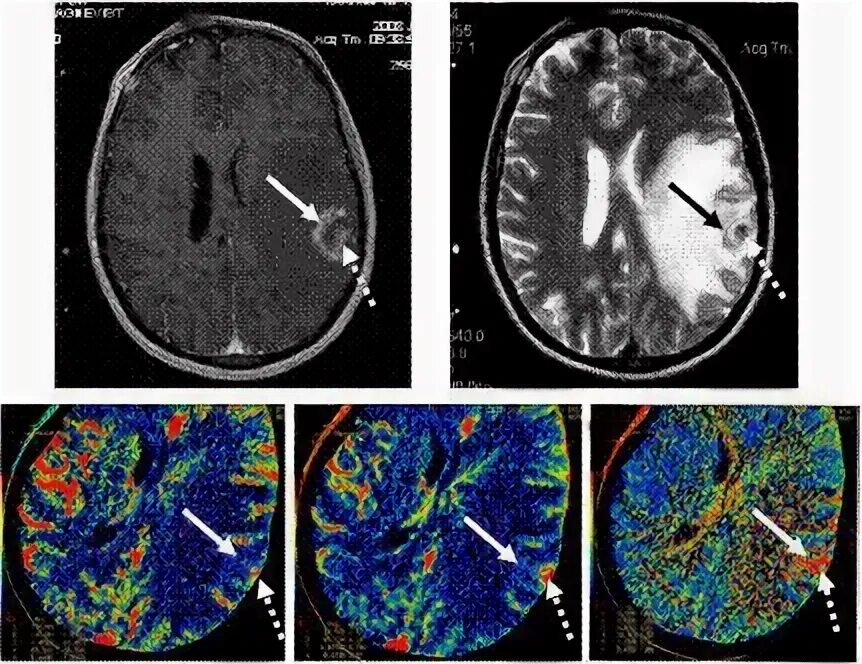

Мрт с контрастом в каких случаях